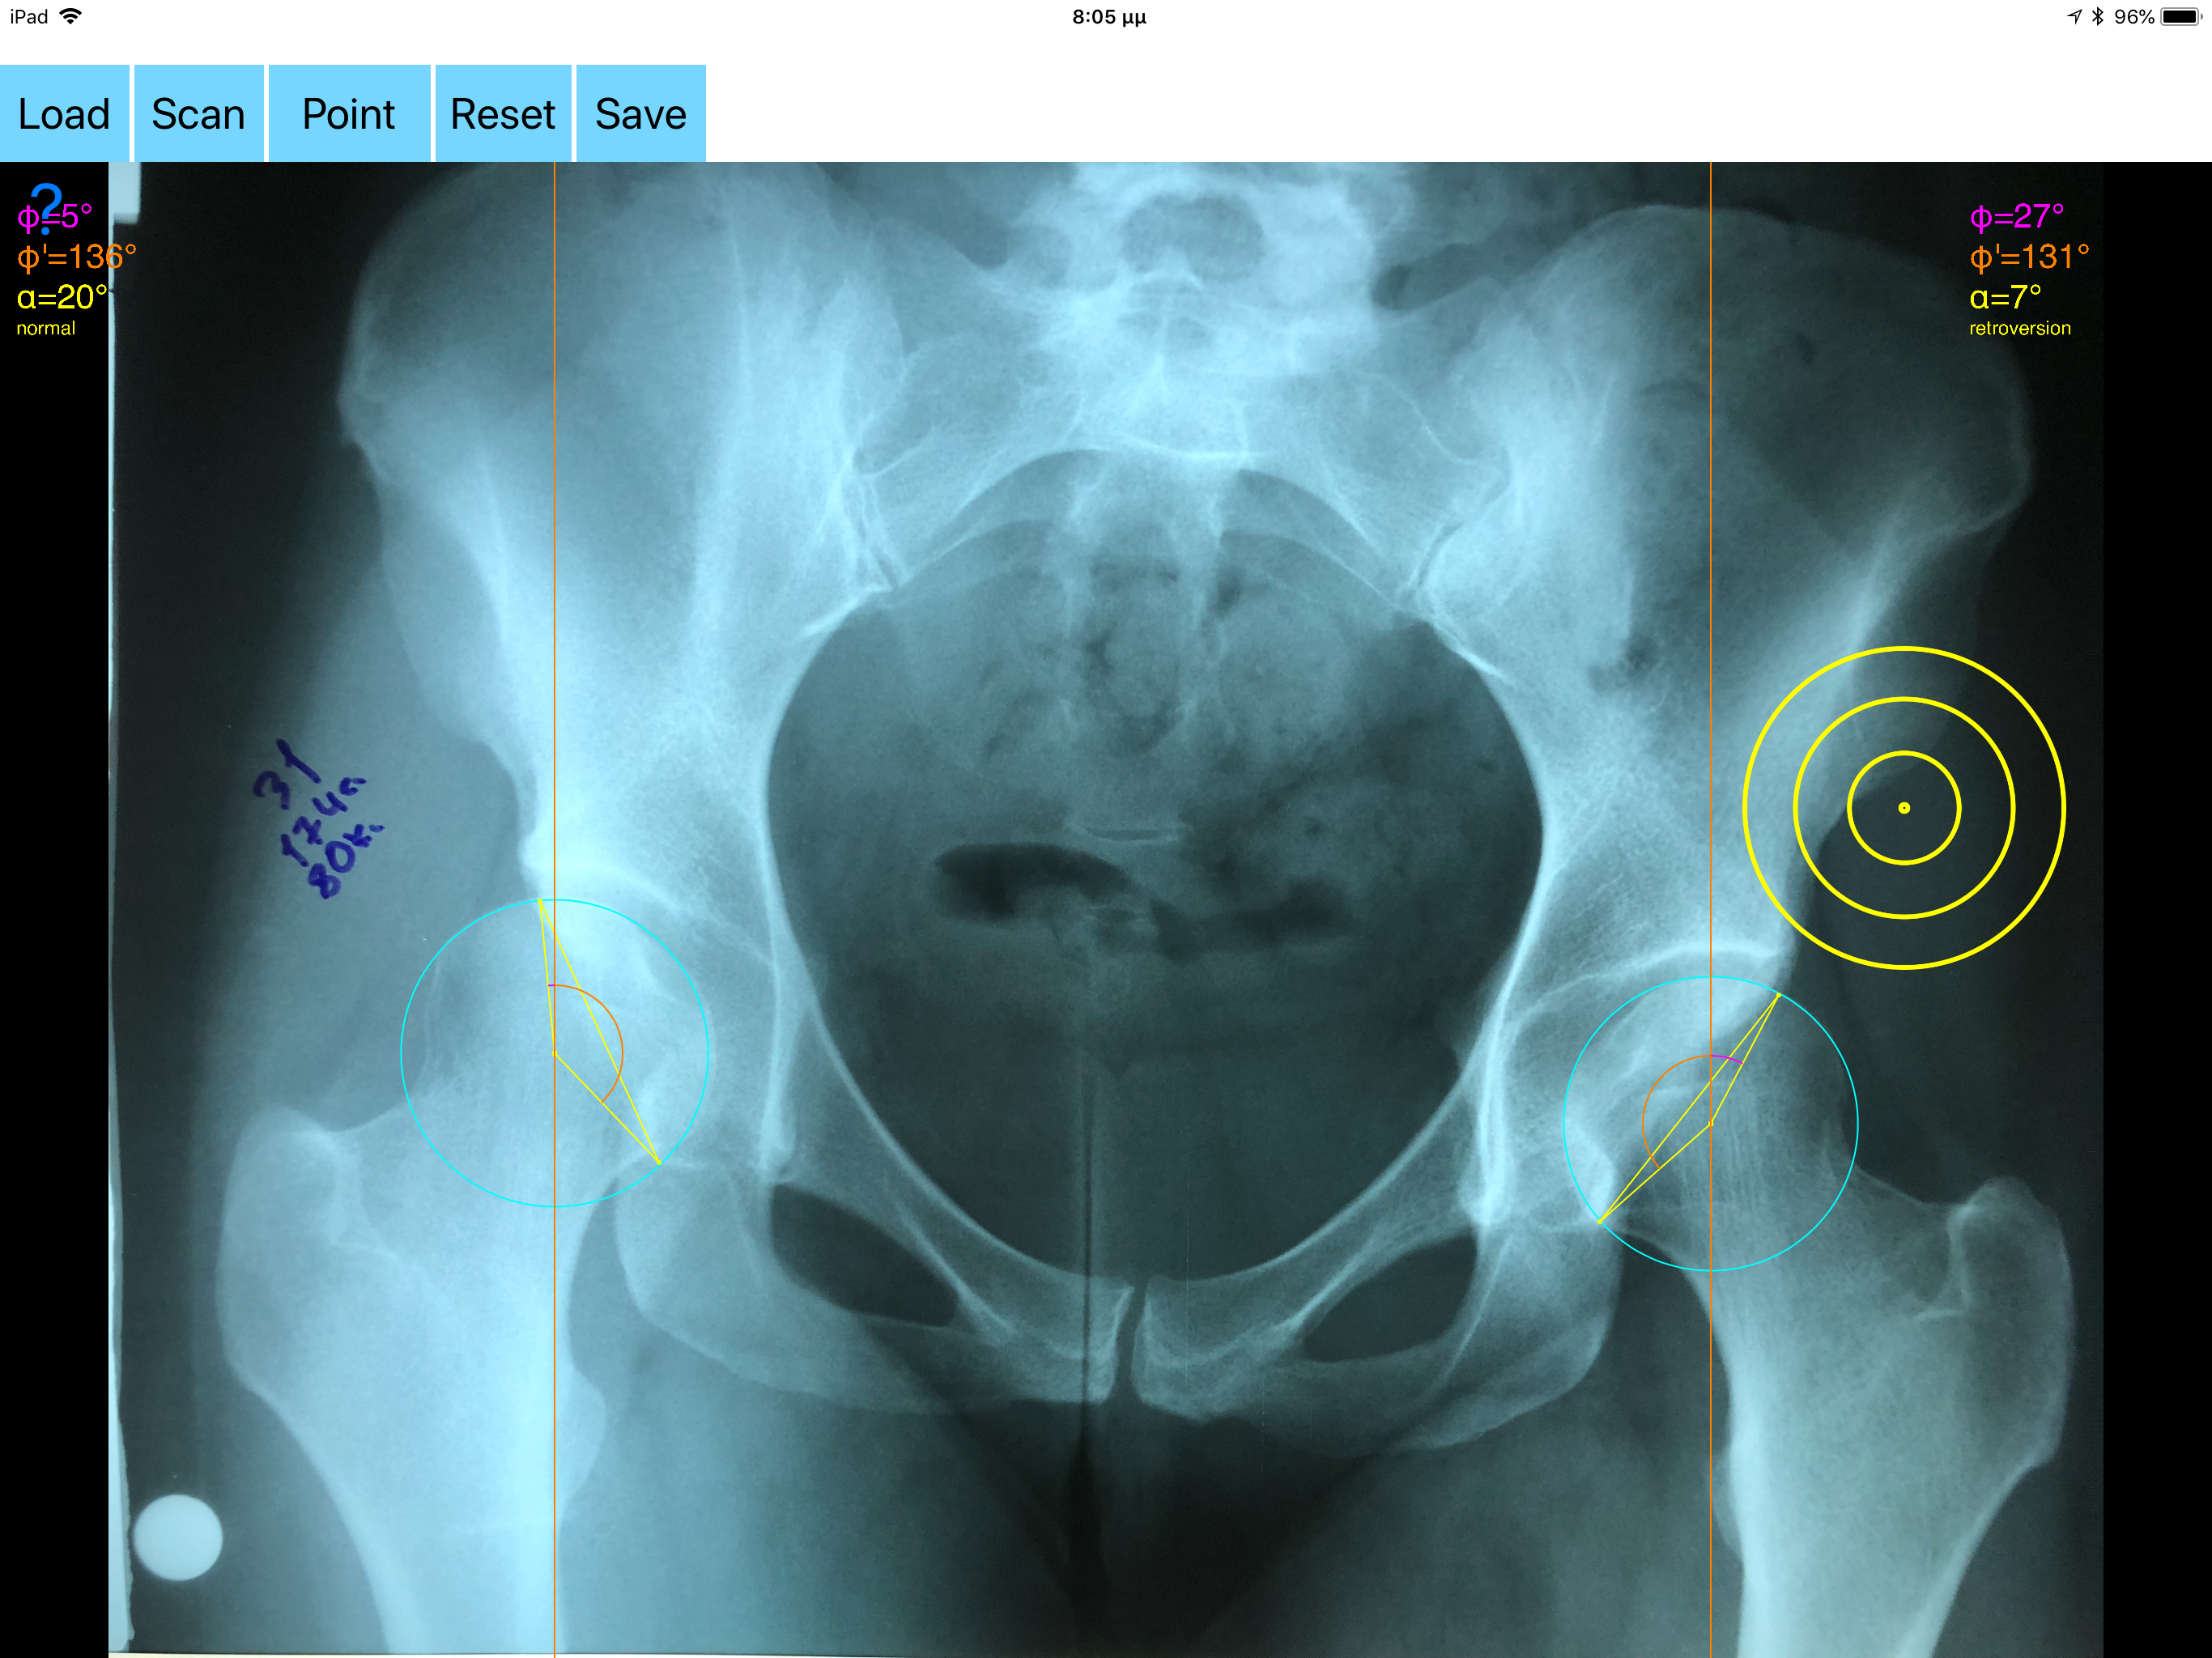

Acetabular version refers to the anteroposterior orientation of the acetabular opening relative to the true horizontal axis of the pelvis. The normal human acetabulum is anteverted in order to allow impingement free range of motion including flexion, adduction, and internal rotation. Abnormal acetabular version has been correlated with pathologic hip conditions including femoroacetabular impingement (FAI) and developmental hip dysplasia.The association between acetabular version and hip pain has been well established in recent years as a source of contributing to early hip osteoarthrosis and labral tears. Recognition and appropriate treatment of abnormal acetabular version is crucial to preventing irreversible damage to the hip Acetabular version is conventionally evaluated on CT scans but excessive radiation doses associated with routine use of computed tomography (CT). An objective radiographic tool which provides measurements comparable in accuracy to CT measurements has been developed by Dr. Hefti (Nomogram).Tedious and time-consuming calculation has to be done in simple X-rays in order to calculate the acetabular anteversion. The primary goal of this App is to help determine radiographic values of acetabular anteversion in a practice in a blink of an eye and avoiding CT scans. The App is medical software aimed for orthopaedic surgeons, providing tools that allow doctors to: -Securely import medical images directly from the camera or stored photos. -By marking certain points in a simple standard AP pelvic radiograph, geometric parameters are being calculated. The App computes the acetabular anteversion based on a pelvic AP radiograph. The angle of anteversion is calculated through the formula according to Heftis nomogram. The acetabular orientation (anteversion/retroversion) is determine by the app by the measurement of the angles between the center of the femoral head and the anterior (φ) and posterior (φ’) acetabular rim. Once you choose correctly the anterior and posterior acetabular rims the app calculates the acetabular anteversion based on nomogram. -The data are printed over to screen so each case can easily assessed -Save the planned images, for later review or consultation. Disclaimer. Regarding its plausibility app offers no diagnosis or treatment. App provide an early indication that further evaluation may be warranted by Speciality Doctor. Explicitly is announced that the apps are not for diagnosis. Clinical judgment and experience are required to properly use the software. App alone do not replace an M.D. or specialist. All information received from the App output must be reviewed before any attempted treatment. The software is not for primary image interpretation. Any influence to the operators in making decisions remains user own responsibility and experience. App does not dispense medical advice. Patient should seek a doctor’s advice in addition using the app and /or before making any medical decisions for themself. Never substitute or replace doctors advice or change treatment modalities based on any measured outcome. App indicated for assisting healthcare professionals for scientific and research reason. Clinical judgment and experience are required to properly use the app and further research and validation is pending in coming future. Reference Friz Hefti, Pediatric Orthopaedics in Practice, Chapter5 , Pelvis hips and thighs 5.3.2.1 Biomechanics of the hip-Book. Springer